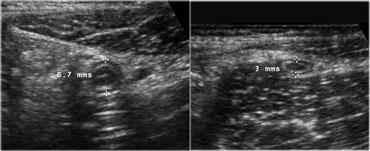

Ruột thừa bình thường

Ruột thừa bình thường có hình ảnh là một cấu trúc nhỏ, dễ đè xẹp, có các lớp đồng tâm, di động, tận cùng mù, hình ống dài như xúc xích.

Đường kính lên đến 7mm được coi là bình thường.

Ruột thừa bình thường có thể di động, lòng ruột có thể xẹp, nhưng cũng có thể chứa khí hoặc một ít chất phân, và hiếm khi chứa một ít dịch (6).

Doppler năng lượng cho thấy tín hiệu mạch máu thưa thớt hoặc không có, và không có lớp mỡ viêm tăng âm, không thể đè xẹp xung quanh ruột thừa.

Viêm ruột thừa cấp. Ruột thừa viêm không thể đè xẹp (đầu mũi tên) nằm cạnh hồi tràng bình thường có thể đè xẹp tốt. Lòng ruột thừa giãn với đường kính 11x13mm. Lưu ý hình ảnh mức dịch-cặn bên trong lòng ruột thừa.

Viêm ruột thừa

Hình ảnh điển hình của ruột thừa viêm là một cấu trúc hình ống dài như xúc xích, có các lớp đồng tâm, không thể đè xẹp, được xác định ở vị trí cố định tại điểm đau tối đa (Hình).

Đường kính tối đa trung bình là 9mm với biên độ dao động từ 7 đến 17mm. Trong 30% trường hợp, sỏi phân (fecolith) trong lòng ruột thừa được tìm thấy gây tắc nghẽn thực sự.